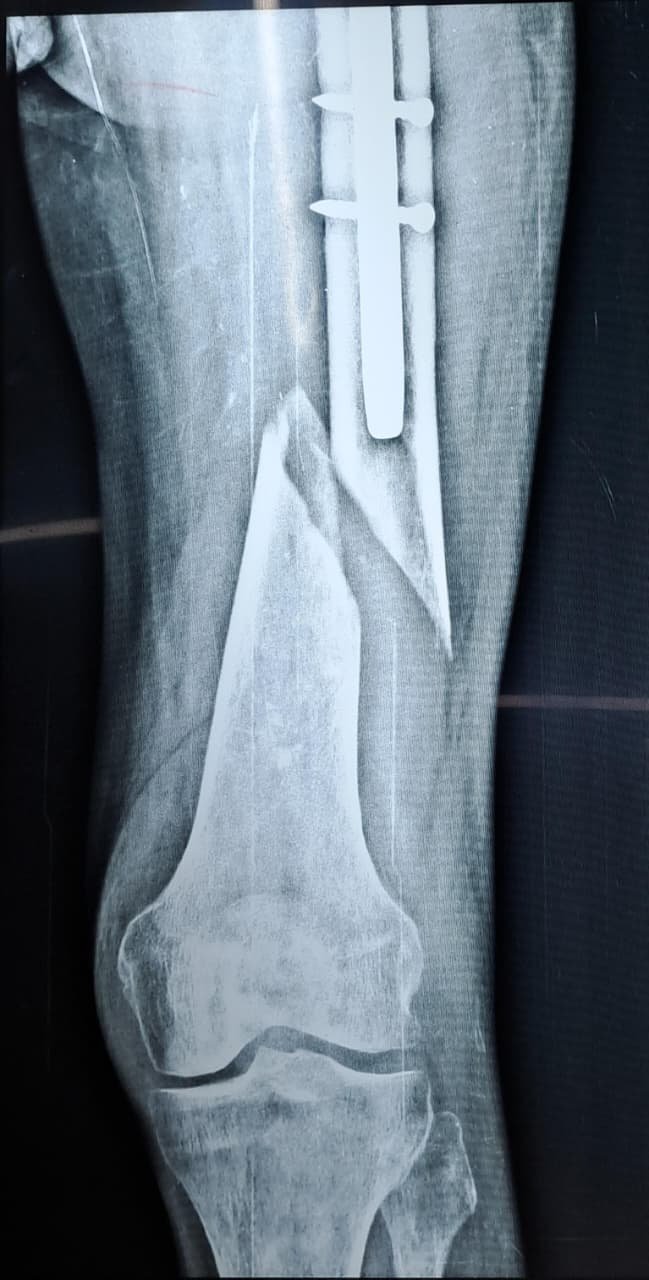

Peri-implant fracture

Atlas ID: 4 • Orthonotes Atlas

Peri-implant Fractures

Peri-implant fractures - Case Based Discussion